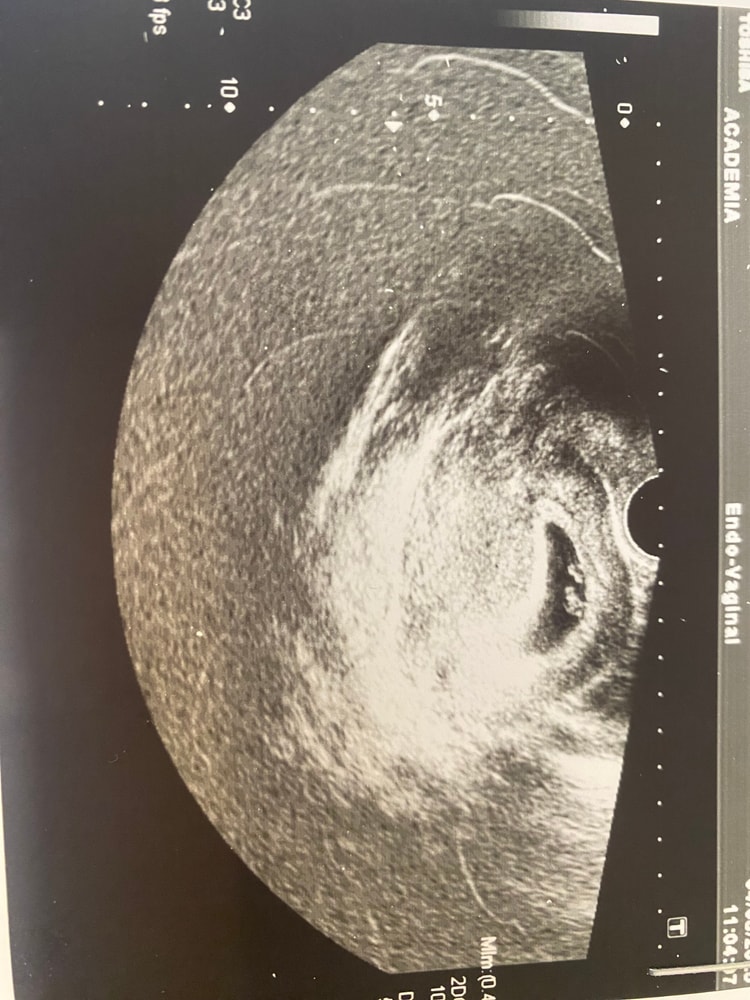

Деля , верхнее 7 недель, нижнее сегодня 8,4 Изображение Изображение

Екатерина , ну по снимку очевидно, что вырос хорошо) Измерили неправильно